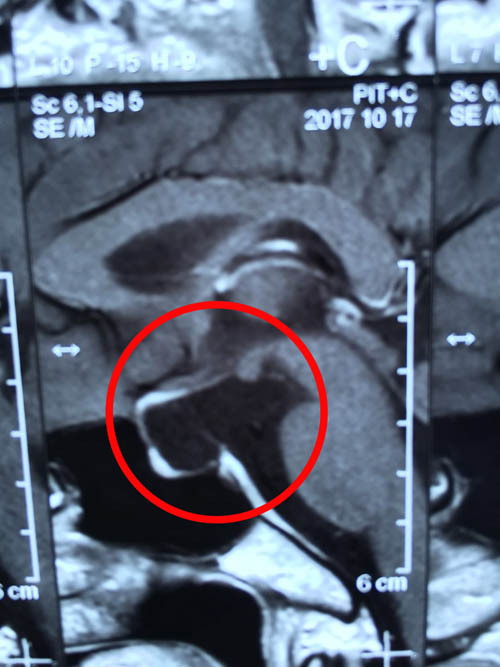

清晰影像之下 “元兇”無可遁形(紅圈內(nèi)即為垂體柄囊腫)